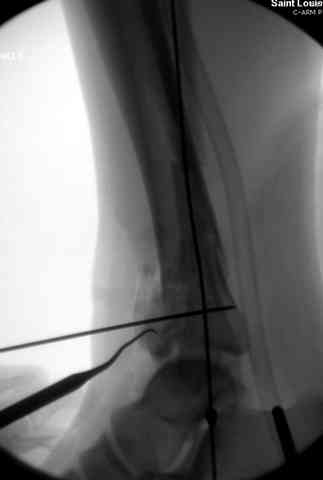

Здесь выставлена пара случаев перелома пилона, оба

случая леченные этапным наружным фиксатором.

Второй случай фиксирован аппаратом Илизарова.